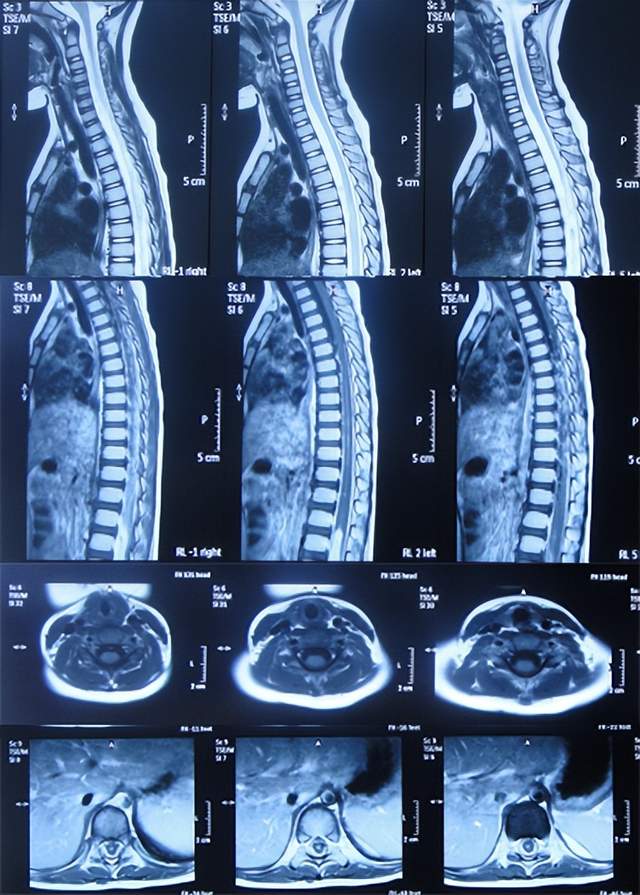

住院治疗7天即2022年5月18日,出现头痛,呕吐,体温再次升高为39.6度,心电图示室性心动过速,室早,考虑“心肌炎”,查头颅核磁(图-1)后并行腰穿见脑脊液呈金黄色,留取脑脊液送常规化验提示诊断为颅内感染,给予抗感染治疗。

图-1:2022年5月18日头颅核磁

在第2家医院治疗13天即2022年5月24日,患儿仍间断高热,在医生建议下当天转至上级的第3家医院山东省某省级三甲医院,查脊髓核磁(图-2)后行腰椎穿刺有脓液吸出,给予腰大池置管术,但未见脑脊液流出,给予消炎、营养脑神经治疗。

图-2:2022年5月24日脊髓核磁